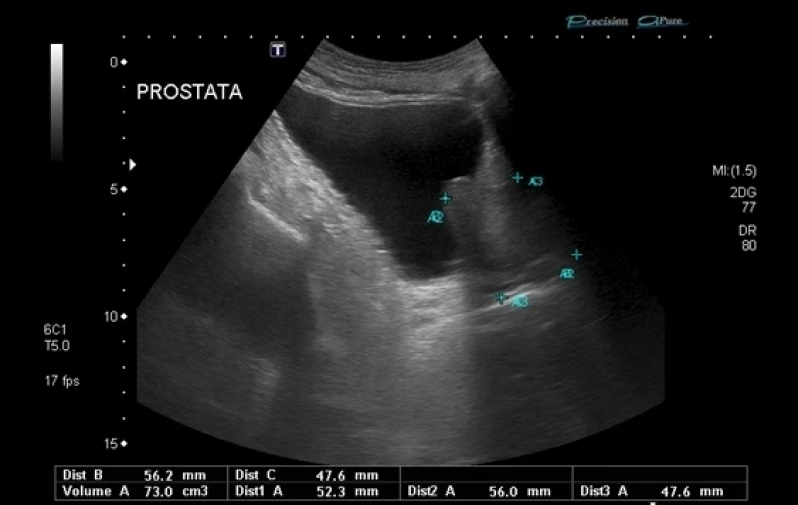

Você busca por biópsia prostática transretal no Itaim Paulista? Saiba que com a DK Urologistas você pode achar serviços como urologistas, vasectomia e cirurgias de fimose, biopsia de próstata, ultrassonografia de próstata, disfunção erétil entre outras opções que são oferecidas para a sua necessidade. Se diferenciado dentro de seu segmento, a empresa consegue também proporcionar um atendimento cuidadoso e que busca a satisfação do cliente.

Os urologistas são médicos especializados no diagnóstico e tratamento de doenças do sistema urinário e reprodutor masculino. Eles tratam desde infecções urinárias até câncer de próstata e disfunção erétil. Além disso, os urologistas também realizam cirurgias para correção de problemas como incontinência urinária e obstruções do trato urinário. É importante que homens e mulheres consultem um urologista regularmente para prevenir e tratar possíveis problemas de saúde. Na DK Urologistas, contamos com uma equipe de profissionais altamente capacitados e equipamentos de última geração para oferecer o melhor atendimento aos nossos pacientes. Agende sua consulta conosco e cuide da sua saúde urológica.